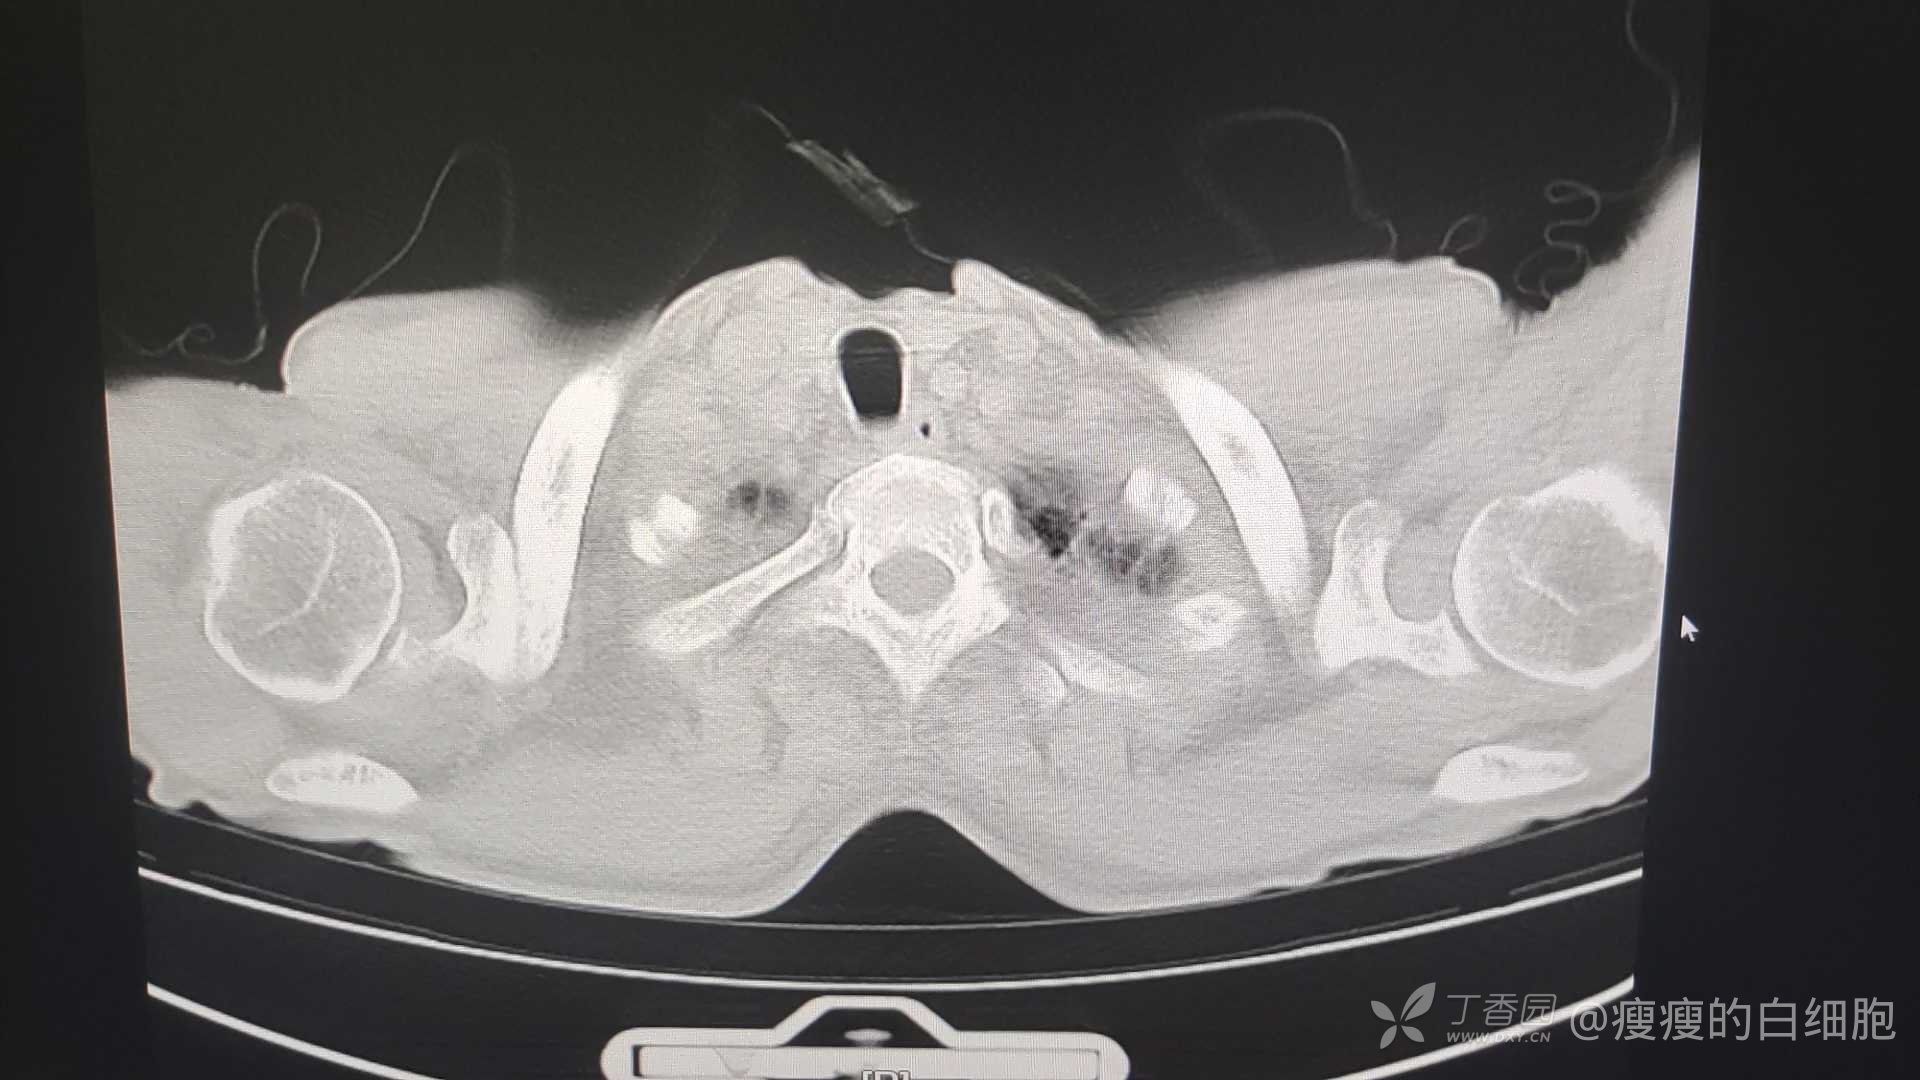

男子,69岁,因发热伴右侧胸痛7天入院,入院时胸部CT如左侧图。

仔细询问病史,一个多月前有轻度咳嗽,未给予抗生素治疗,右图为一个多月前。入院后T-spot阴性,肝功能轻度异常,白蛋白明显下降,达28.5g/L,降钙素原阴性,Ca125明显增高,达117.60U/ml,其余肿瘤指标均正常。入院后体温正常,7天复查胸部CT炎症有所吸收,再过8天复查,肺部斑片影无明显变化。而且患者仍有右侧胸痛。把最后一次复查胸部CT的情况发出来,